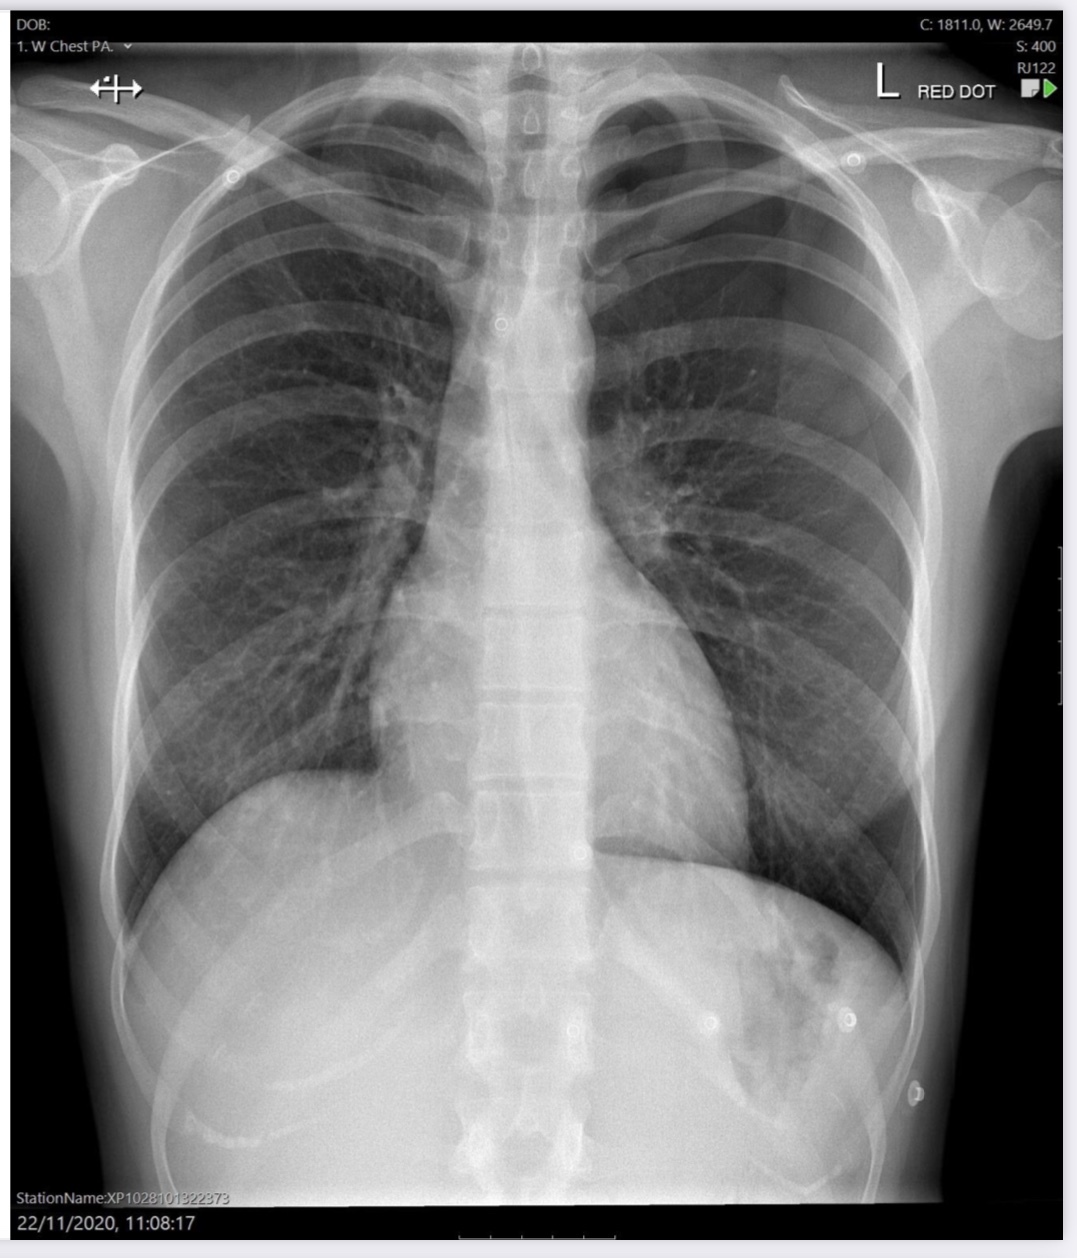

Normal

Correctly placed NG tube